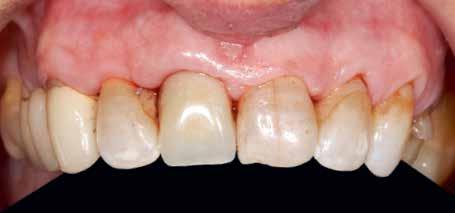

A 2020 januárjában elkezdett kezeléssorozat befejezését az év márciusában, hazánkba is begyűrűző Covid-19 pandémia késleltette, így kb. 6 hónap gyógyulás után láttunk hozzá az emergencia profil és a gingivális zenit ideiglenes koronával történő formázásához (11. és 12. kép). A 3 hetente végzett apró alakításokkal sikerült megfelelő ínyprofilt kialakítani, a „rózsaszín esztétika” a páciens számára is megfelelő volt. A bal felső nagymetsző fog meziális kompozit tömés cseréjét követően, individualizált nyitott kanalas lenyomati fejet készítettünk: az akrilát ideiglenes korona profilját átlátszó szilikonnal lemásoltuk, majd a körszimmetrikus gyári lenyomati fej és az ideiglenes korona kontúrja közötti hézagot folyékony kompozittal töltöttük ki (13. kép). Az így készített egyéni lenyomati fejjel vettünk lenyomatot a végleges, kerámialeplezésű cirkónium-dioxid vázas, átmenő csavaros rögzítésű koronához. (A fogtechnikai munkát Nébl Péter fogtechnikusmester készítette.), (14., 15., 16 és 17. képek).

A kész korona átadásakor a páciens elégedett volt az esztétikával, az azóta eltelt évben rendszeres kontrollokon jelent meg, melyek során meggyőződtünk a kemény- és lágyszövetek stabilitásáról (18. és 19. képek).